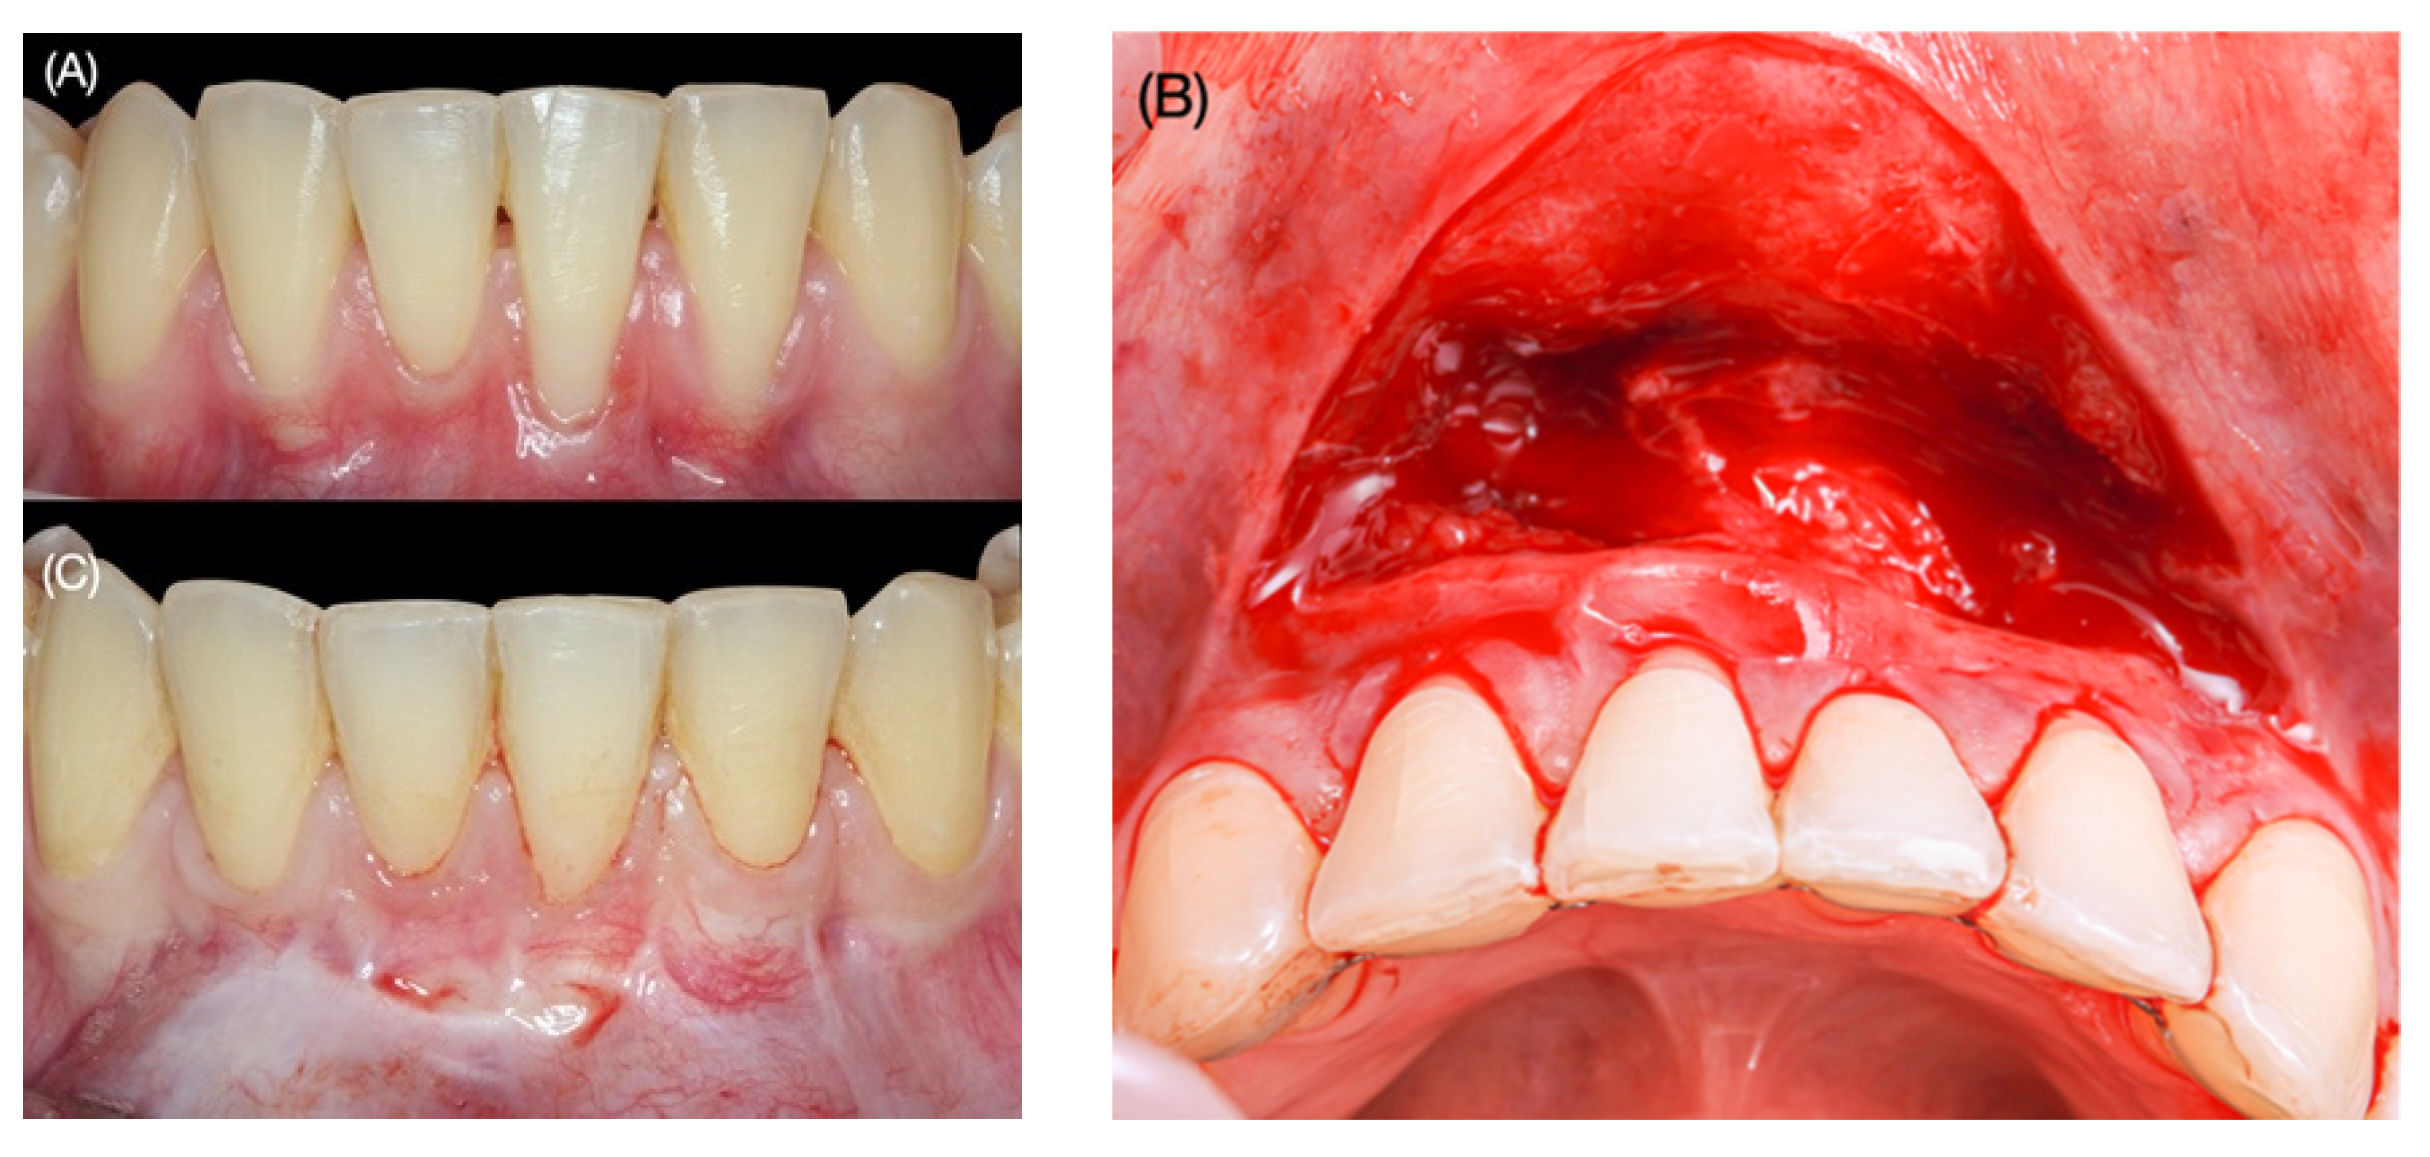

2.1. Surgical Protocol